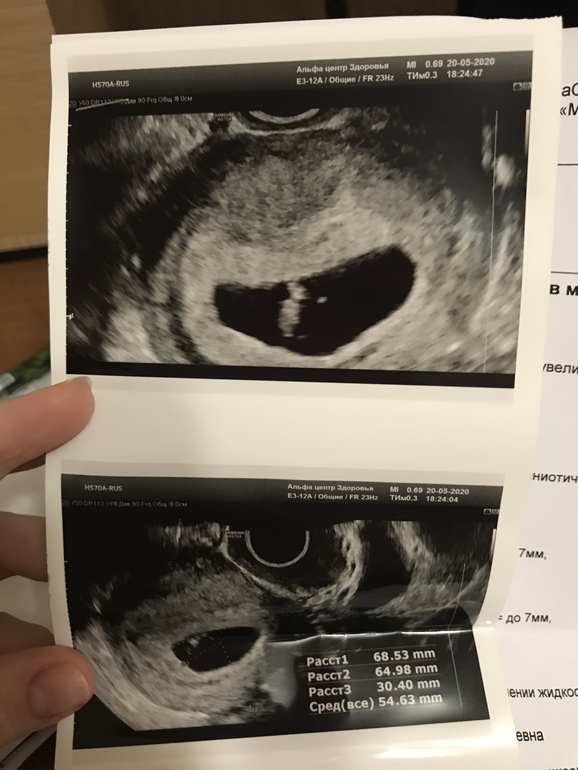

Когда была на узи 11 числа было ровно 6 недель и было только ПЯ 10 мм и жм 3 мм

У нас все хорошо мы ровно по сроку 7 недель

Пя стало 30 мм было 10

Амниотический мешок, то есть плацента 6 мм была 3 мм

Размер крошки и сб не сказали сколько в этой клинике не говорят

Но моя г сказала все отлично и он где-то 6 мм так как он во весь этот мешочек, который 6 мм